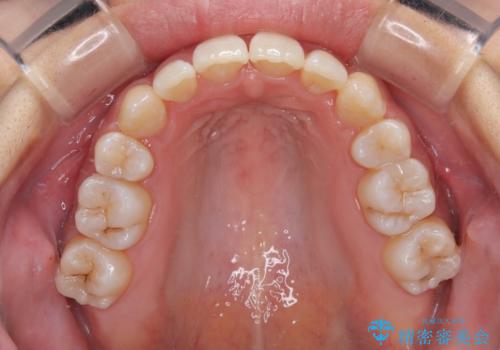

八重歯を改善 ワイヤー装置での抜歯矯正

下顎歯列の叢生は軽度であることと、口元の突出感が全くなかったことから、八重歯解消のために上顎左右第一小臼歯を抜歯し、ワイヤー装置にて矯正治療を行うこととしました。

八重歯をスムーズに解消するために、補助装置を用いることで速やかに歯列を整えることができました。